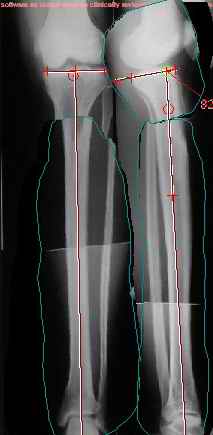

Продолжение обсуждения, начатого в октябре прошлого года (см. здесь) Наконец-то оперировали эту пациентку. Биопсию сделали - опухолевого ничего нет. Пока все участвовавшие в обследовании смежные специалисты и ортопеды сошлись, что это молокальная монооссальная фиброзная дисплазия. 20 марта наложили аппарат, сделали чрескожную остеотомию. К 3 апреля все докрутили. Сегодня заштифтовали. Начальные и итоговые снимки в приложении. Рекурвацию можно было еще немного больше устранить, и чуть кзади сместить диафиз. Но вроде и так ничего выглядит, по сравнению с тем, что было. Комментарии приветствуются.

ничего не понимаю в детской и ортопедии, но в боковой проекции нет рекурвации,

а даже немного гиперкоррекция, что по-моему есть хорошо. Кортикалы по задней стенке совпадают, диафиз на одну неправду кзади.